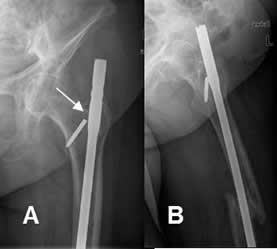

Fig 110. Salida material.

A: Rx AP y B: Rx lateral. Clavo endomedular, fijando una fractura del fémur. Hay ruptura en el tornillo, el cual está desplazado inferiormente.